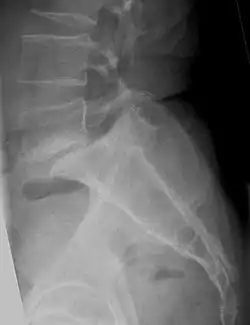

![]() صورة أشعة سينية لانزلاق الفقارات. صورة أشعة سينية لانزلاق الفقارات. | |